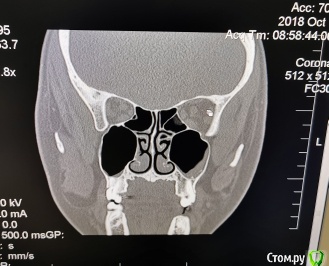

olga.maverick Опубликовано 1 марта, 2021 Поделиться Опубликовано 1 марта, 2021 (изменено) Здравствуйте!Вместо удалённого год назад зуба, 18 февраля врач установил мне в верхнюю челюсть имплант Импро, без синус лифтинга, сказал, что между слизистой и имплантом проложил губку, она рассосётся и кость нарастёт. Он сделал контрольный снимок-рентген, подтвердил, что имплант в пазухе, но под слизистой и это по его мнению норма. Пять дней я пила Амоксиклав по его назначению. Сегодня, первого марта сделала снимок КЛКТ, т.к. не проходит. насморк и дискомфорт в районе пазух.Получилась вот такая картина-сильный отёк в районе правой пазухи , до установки импланта отёка не было, есть снимок, сделанный перед операцией. Помогите пожалуйста разобраться:1) Всё идёт по плану, отёк временная реакция, имплант установлен профессионально или всё плохо?2)Нормально ли, что имплант стоит не посередине, а впритык к одному зубу? Изменено 1 марта, 2021 пользователем olga.maverick Ссылка на комментарий

olga.maverick Опубликовано 1 марта, 2021 Автор Поделиться Опубликовано 1 марта, 2021 (изменено) И, ещё, уважаемые доктора, если позволите вопрос. В левой пазухе у меня отёк уже несколько лет. Один маститый лор сказал, что у меня киста и он мне её удалит. Другой оперирующий лор сказал, что кисты нет, есть пломбировочный материал под слизистой, внутри пазухи ничего нет, кроме отёка слизистой.Мой врач (речь о котором в посте выше) утверждает, что в 27 зубе, максимально близко подходящем к пазухе, нет пломбы, зуб девственный. А я не помню, что и когда лечила. У вас есть версии, что за крапинка на снимке в левой пазухе и кому идти за решением, к лору или стоматологу)? Маюсь хроническим ринитом и периодическими гайморитами. Изменено 1 марта, 2021 пользователем olga.maverick Ссылка на комментарий